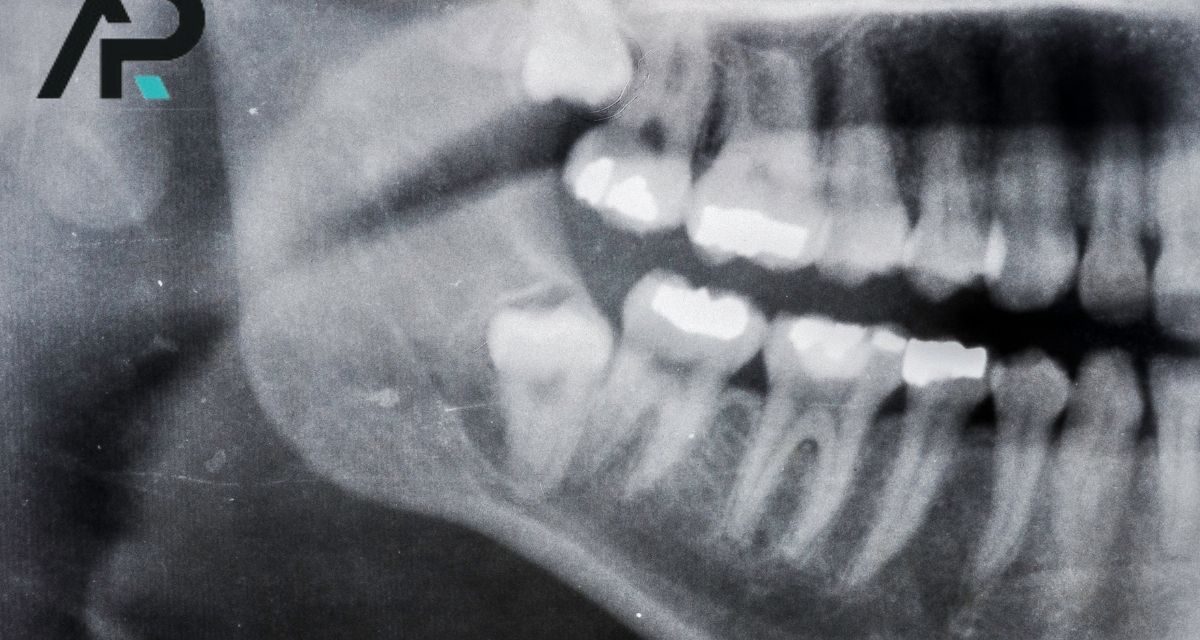

DentAP Grup Ağız ve Diş Sağlığı Polikliniği, Malatya çene cerrahisi alanında uzman hekim kadrosu ve modern tıbbi altyapısıyla hizmet vermektedir. Çene cerrahisi Malatya bölgesinde sadece estetik amaçlarla değil, aynı zamanda fonksiyonel sorunların giderilmesinde de büyük önem taşır. Kliniğimizde gerçekleştirilen işlemler; diş, çene, yüz ve ağız bölgesinde gelişen her türlü sorunun tanı ve cerrahi tedavisini kapsar....